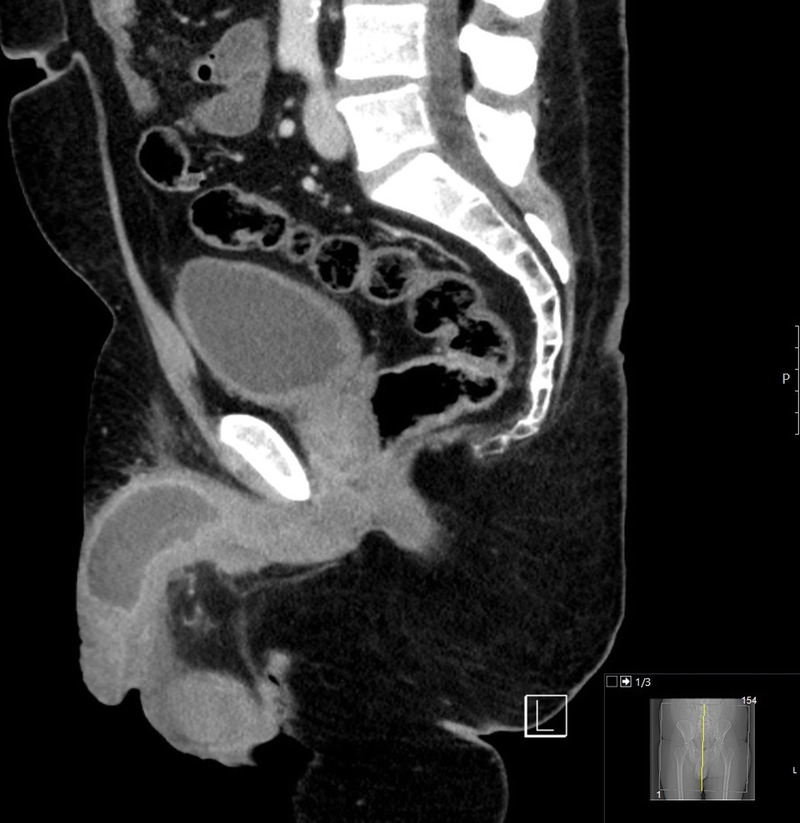

常规泌尿外科术后海绵体脓肿。

Cavernosal abscess after routine urological surgery.